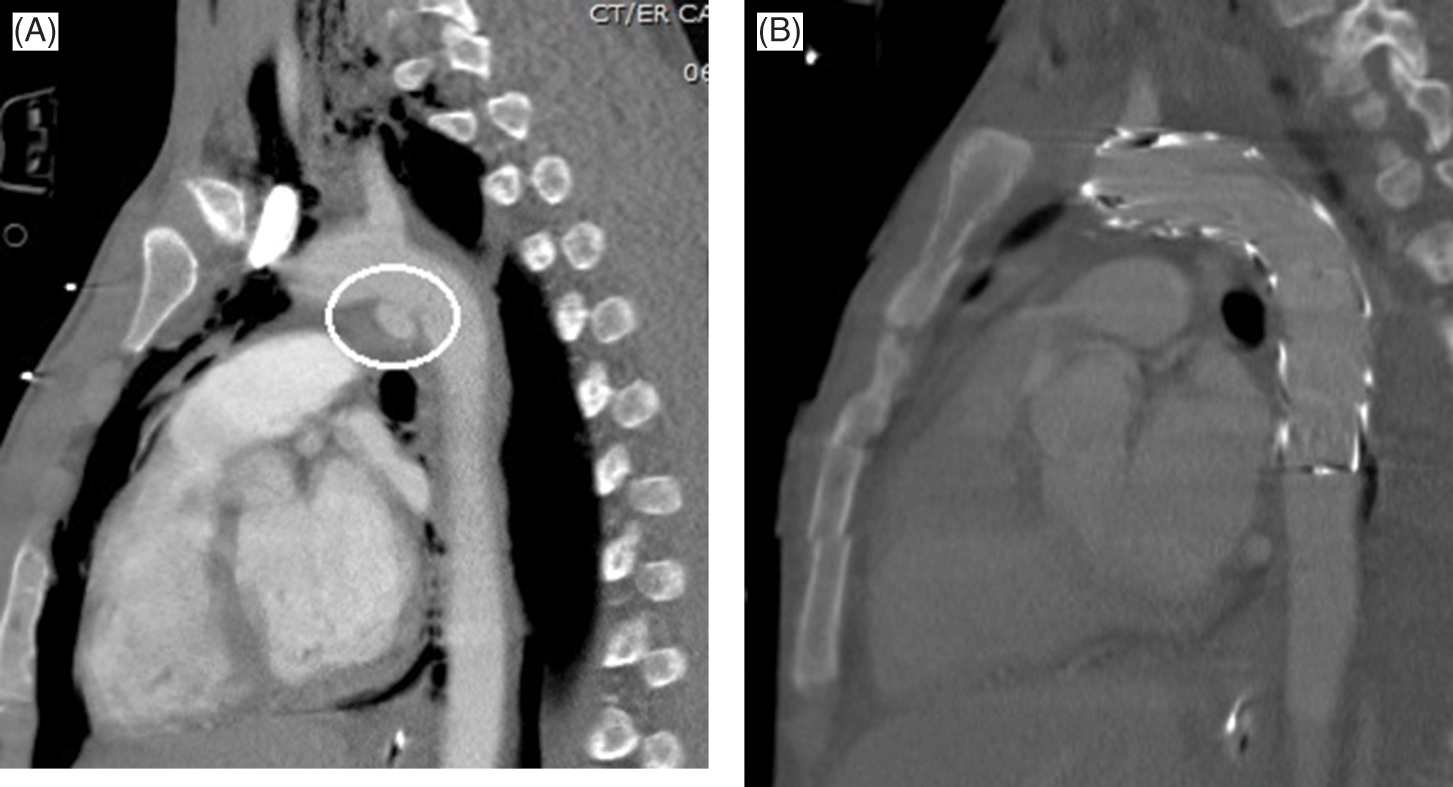

Pocket Atlas of Head and Neck MRI Anatomy: Lufkin, Robert B, Axial CT scan of the atlas immediately after trauma (A) and,

Raise the standard in MRI - FieldStrength MRI | Philips, Thoracic Injury (Chapter 4) - Color Atlas of Emergency Trauma,

Thoracic Injury (Chapter 4) - Color Atlas of Emergency Trauma, Etiology of Cortical and White Matter Lesions in Cyclosporin